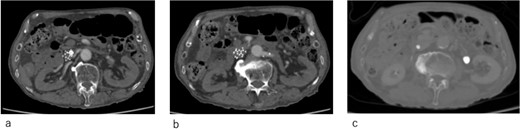

An IVCF was inserted into the inferior vena cava (IVC) using the right internal jugular venous approach. After performing IVC venography (Fig. 2a) using a driver sheath, the IVCF was attempted to deployed. However, the IVCF did not open (Fig. 2b). To retrieve the unopened filter, a plunger was pulled; however, the IVCF and plunger detached (Fig. 2c). We attempted to remove the IVCF via a right femoral venous approach using a snare. However, the snare did not pass through the IVCF because the tip of the leg was attached to the IVC wall or gonadal vein ostium. The hemodynamics of the patient worsened during the procedure. Therefore, we decided to quit additional endovascular retrieval and place a new IVCF. A new IVCF was placed to hold the unopened IVCF at the proximal (head) portion of the unopened IVCF through a right jugular approach (Fig. 2d). An unopened IVCF was placed with pulling the delivery sheath (Fig. 3).

Intraoperative radiographic fluorescence imaging. (a) Pre-deployment venogram of the inferior vena cava (IVC) demonstrating appropriate positioning of the delivery sheath within the IVC prior to inferior vena cava filter (IVCF) placement. (b) The IVCF is not open, and the legs of the IVCF are folded. The IVCF is hung on a plunger. The arrow indicates the tip of the sheath. The arrowheads indicate the folded IVCF legs. (c) The IVCF could not be retrieved because it is detached from the plunger. The arrow indicates the tip of the sheath. The arrowheads indicate the folded IVCF legs. (d) The new IVCF is deployed proximal to the old IVCF.

Abdominal X-ray image after the surgery. Two inferior vena cava filters are placed.